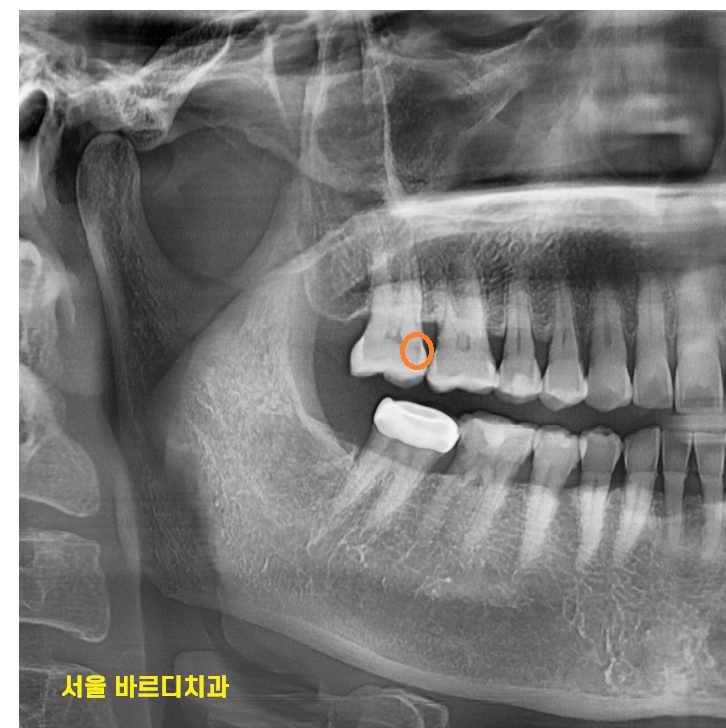

오른쪽 위에 치아가 씹는게 가끔 불편하다 하셨습니다.

x-ray 상에 충치가 일부 먹은게 보여서

치아를 확인해봤더니

230708

하얗게 보여야할 부분인데

까만 것이 비쳐 보였습니다.

하필 부위가 치아 사이 충치라 치료하기가 ㅠㅠ